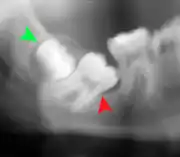

If the tooth cannot be assessed with clinical exam alone, the diagnosis is made using either a panoramic radiograph or cone-beam CT. Where unerupted wisdom teeth still have eruption potential several predictors are used to determine the chance of the teeth becoming impacted. The ratio of space between the tooth crown length and the amount of space available, the angle of the teeth compared to the other teeth are the two most commonly used predictors, with the space ratio being the most accurate. Despite the capacity for movement into early adulthood, the likelihood that the tooth will become impacted can be predicted when the ratio of space available to the length of the crown of the tooth is under 1.[5]: 141